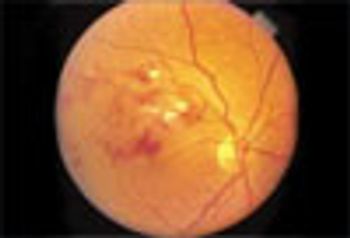

To what cause of sudden loss of vision do the funduscopic findings point?